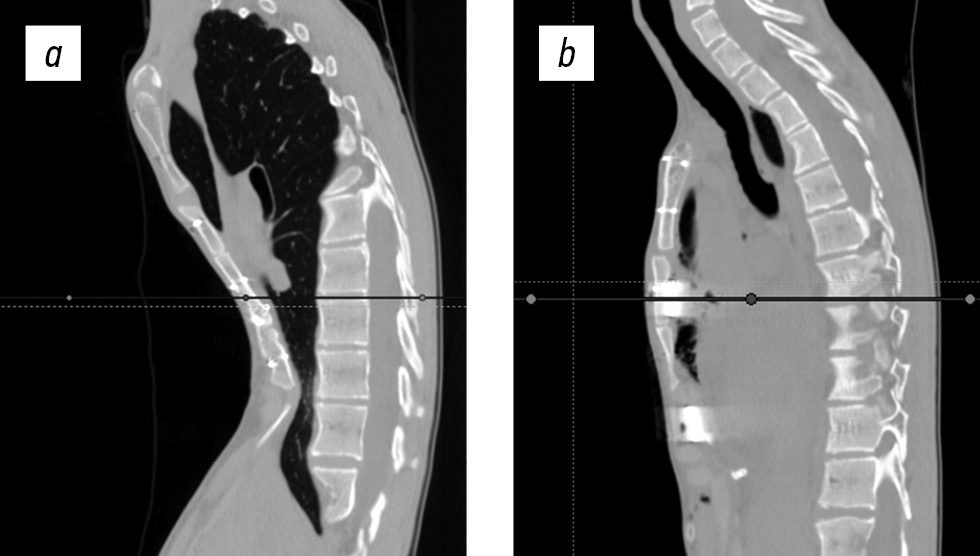

Плановое обследование включало обзорную рентгенографию грудной клетки в переднезадней проекции через сутки, а также на 5-й и 10-й день от момента операции, компьютерную томографию грудной клетки через трое суток после вмешательства. После проведения компьютерной томографии грудной клетки и вертикализации два дренажа удалены, правый плевральный дренаж удален на пятые сутки после дополнительного рентгенологического контроля (рис. 5, 6).

Рис. 5. Компьютерные томограммы до и после коррекции: a — исходный размер ретростернального пространства, до операции; б — контрольное исследование на 5-е сутки после операции.

Рис. 6. Компьютерные томограммы до и после коррекции: a — до операции; б — 5-е сутки после операции.